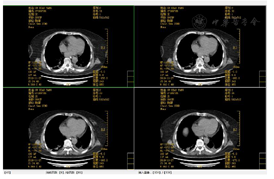

2019年8月3日急诊头颅CT提示:右侧脑出血,伴蛛血(图1)。2019年11月27胸日部CT提示:肺部感染,部分实变(图2、图3)。呼吸功能评估:胸廓活动度明显下降,呼吸肌肌力和耐力下降,无自主咳嗽。绿染实验提示患者有误吸,无食道反流情况。吞咽功能评估:存在误吸,咳嗽力量欠佳,口腔运送能力差,吞咽启动明显延迟,咽缩肌无力,下颌运动受限。

4.治疗中期及拔管前功能评估:未吸氧,血氧饱和度正常范围,生命体征平稳。主动张口幅度1.5 cm,被动张口幅度2.5 cm,自主咳嗽能力正常、自主清嗓较稍减弱,咽反射正常,吞咽启动减慢,喉上抬范围1.0 cm,简易吞咽诱发试验正常。气切管固定稳妥,未见异常分泌物。经气切口通气,呼吸平稳;膈肌移动度及呼吸肌肌力和耐力正常。Brunnstrom运动功能评定:左上肢3期、左手3期、左下肢4期。左侧肢体浅感觉较对侧减退,左肘及左膝关节平面以下感觉减弱。颈部被动活动无明显受限。站立平衡1级及坐位平衡2级。完善吞咽造影检查:可进食1、2、3号食物,吞咽造影提示患者吞咽启动减慢,吞咽耐力部分下降(视频2)。拔管前辅助检查评估:(1)完善颈部CT未见颈部无软组织肿胀及呼吸道受压;(2)电子鼻咽喉镜未见气道狭窄,声门开放可(视频3);(3)未吸氧情况下血气分析未见明显异常,肺功能大致正常;(4)肺部CT(图4、图5)提示感染基本控制,炎症明显吸收,血感染指标正常;(5)连续堵管训练24 h,患者血氧饱和度及血气分析正常。